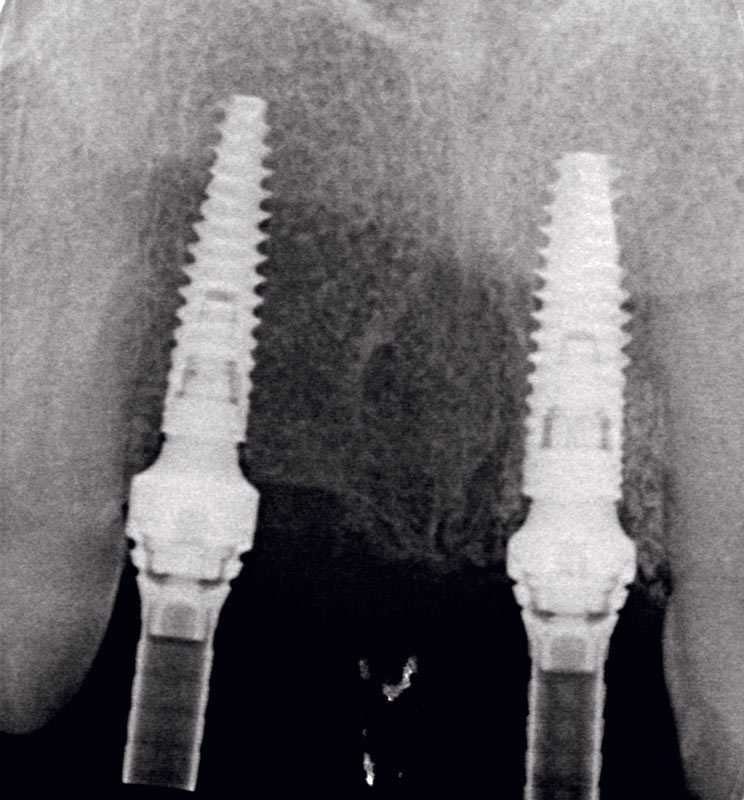

16/17 - Radiographic control.

Socket preservation using cerabone® and Straumann® Emdogain® - Dr. S. Pelekanos